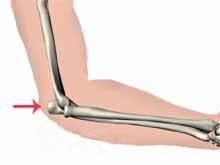

【發病機理】

間接外力。摔倒時肘關節處於關伸直位,外力傳達至肘,肱三頭肌牽拉而造成撕脫骨折。骨折線可能為橫斷或斜行。兩骨折端有分離。直接外力。摔倒時肘關節伸直拉著地,或直接打擊到肘後,造成粉碎骨折,骨折端多無分離。骨折分類尚無共同接受的觀點,北京積水潭醫院,將骨折分為下述幾種。